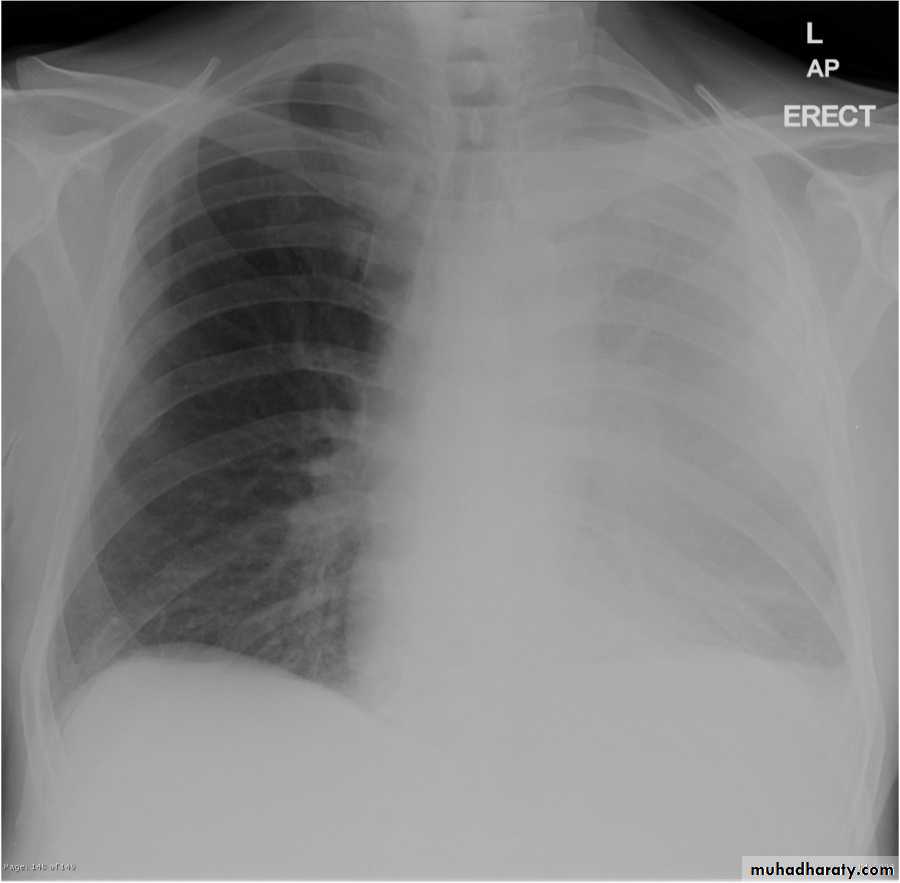

48.opasified hemi thorax Total collapse

Homogenus opacity of the right hemithorax with shifting of the trachea to the same side48.opasified hemi thorax Total consolidation

Homogenus opacity of the left hemithorax with central trachea

Total collapse

Homogenus opacity of the left hemithorax with shifting of the trachea to the same sidePleural effusion

Homogenus opacity of right lower zone with meniscus signOblitration of right cardiophrenic and costophrenic angles

Homogenus opacity of the right hemithorax

Oblitration of cardiophrenic and costophrenic angles

Shifting of the trachea to the opposite side

Pleural effusion

Homogenus opacity of right lower lobe with Oblitration of right cardiophrenic and costophrenic angles.

Meniscus sign